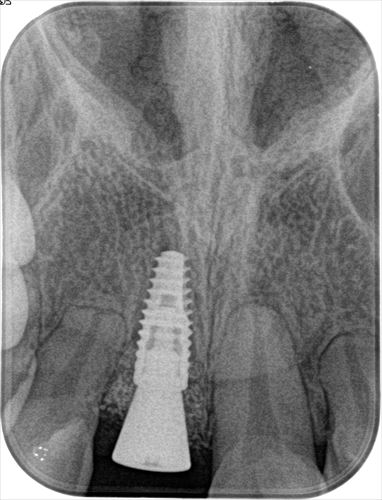

この時点でレントゲン写真を撮ります。

_

撮影したデンタルレントゲン写真です。

この後、仮歯を戻します。